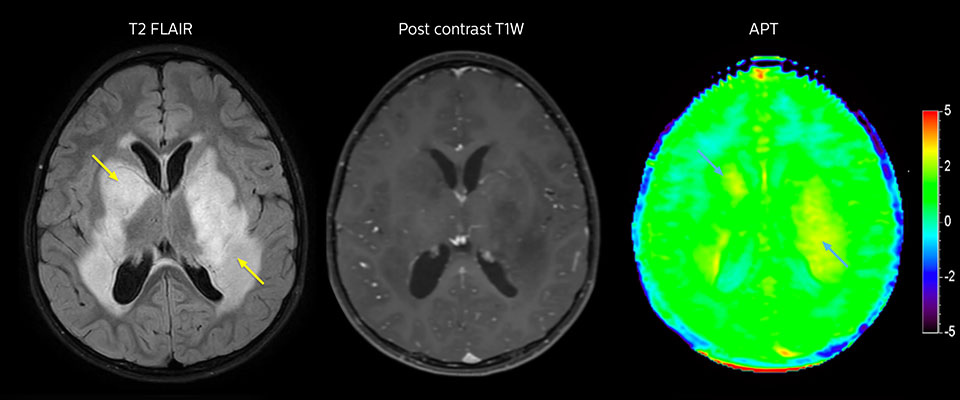

APT-Bildgebung eines niedrig differenzierten Tumors

Niedrig differenziertes Gliom bei einem 5-jährigen Patienten mit Neurofibromatose 1. Diese niedrig differenzierte Läsion zeigt auf kontrastverstärkten Bildern keine Anreicherung, aber ein mittelgradiges APT-Signal. Die Stabilität der Läsion über die Zeit bestätigt, dass es sich um eine pathologische Veränderung niedriger Differenzierung handelt.